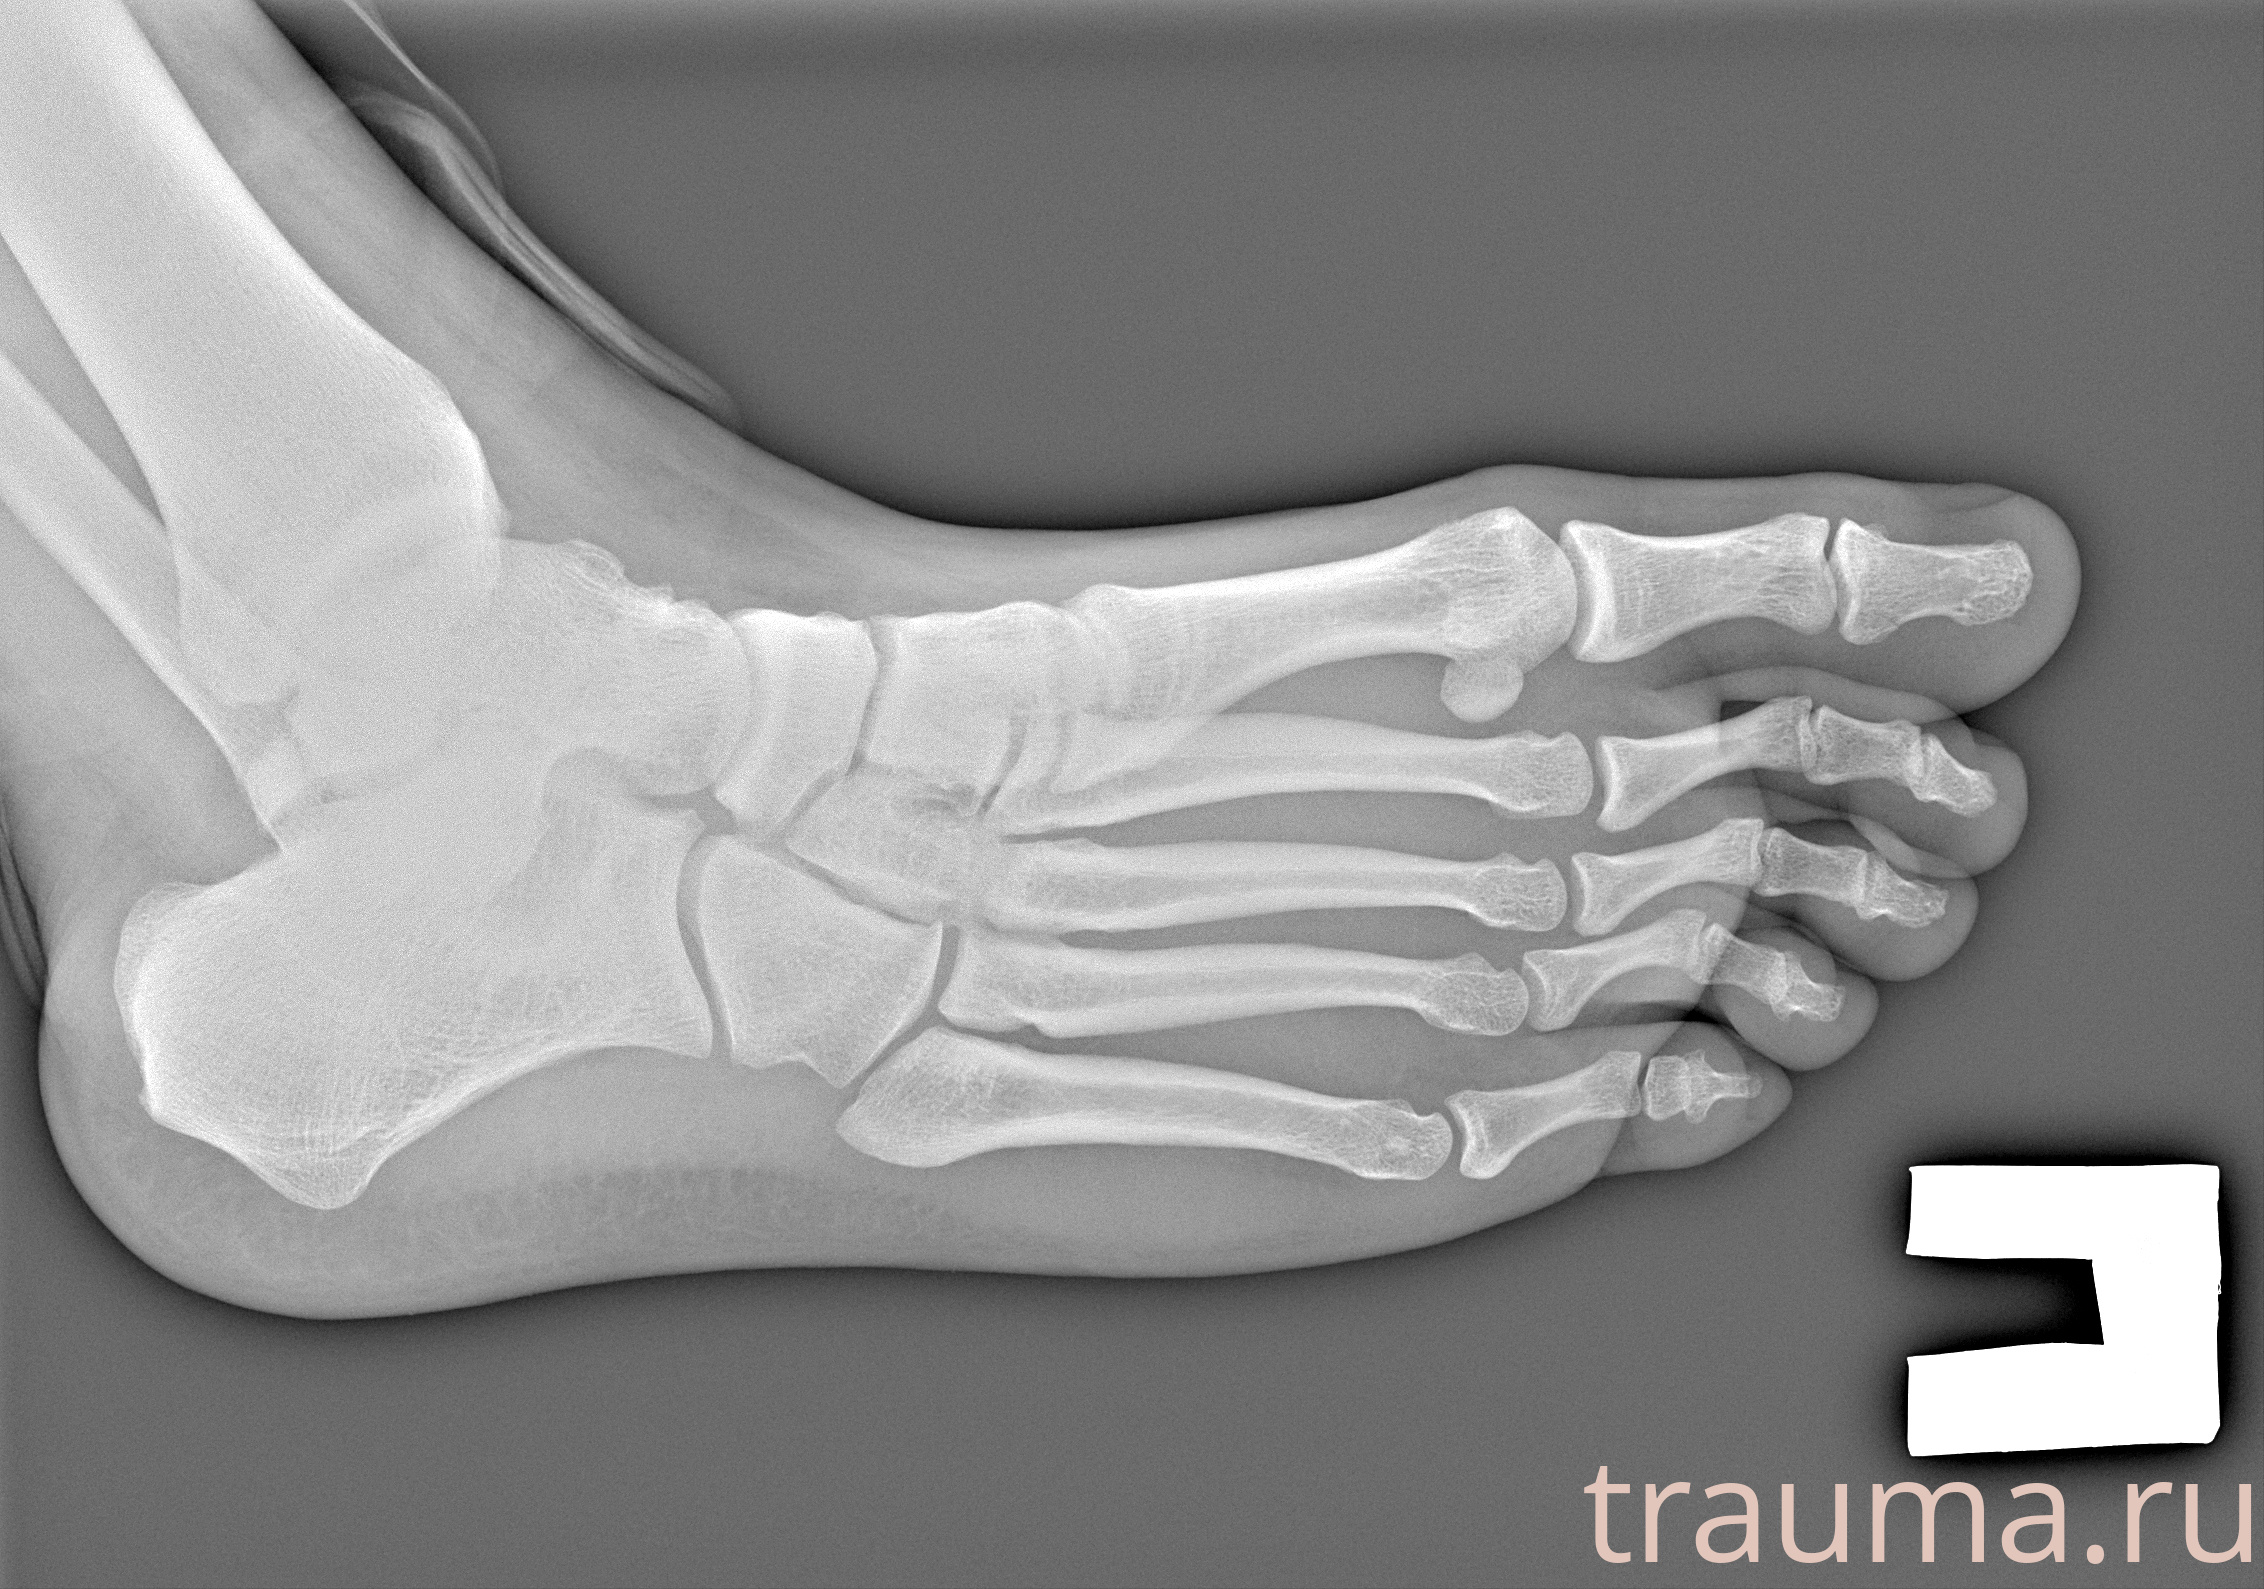

Рентген на дому: по вашему адресу приезжает врач-рентгенолог, травматолог-ортопед с мобильным рентгеновским аппаратом, проводит диагностику травмы или заболевания, делает необходимые рентгенограммы, дает рекомендации по дальнейшему лечению. Получить качественные снимки в домашних условиях возможно благодаря уникальной методике, разработанной МосРентген Центром для института  Склифосовского